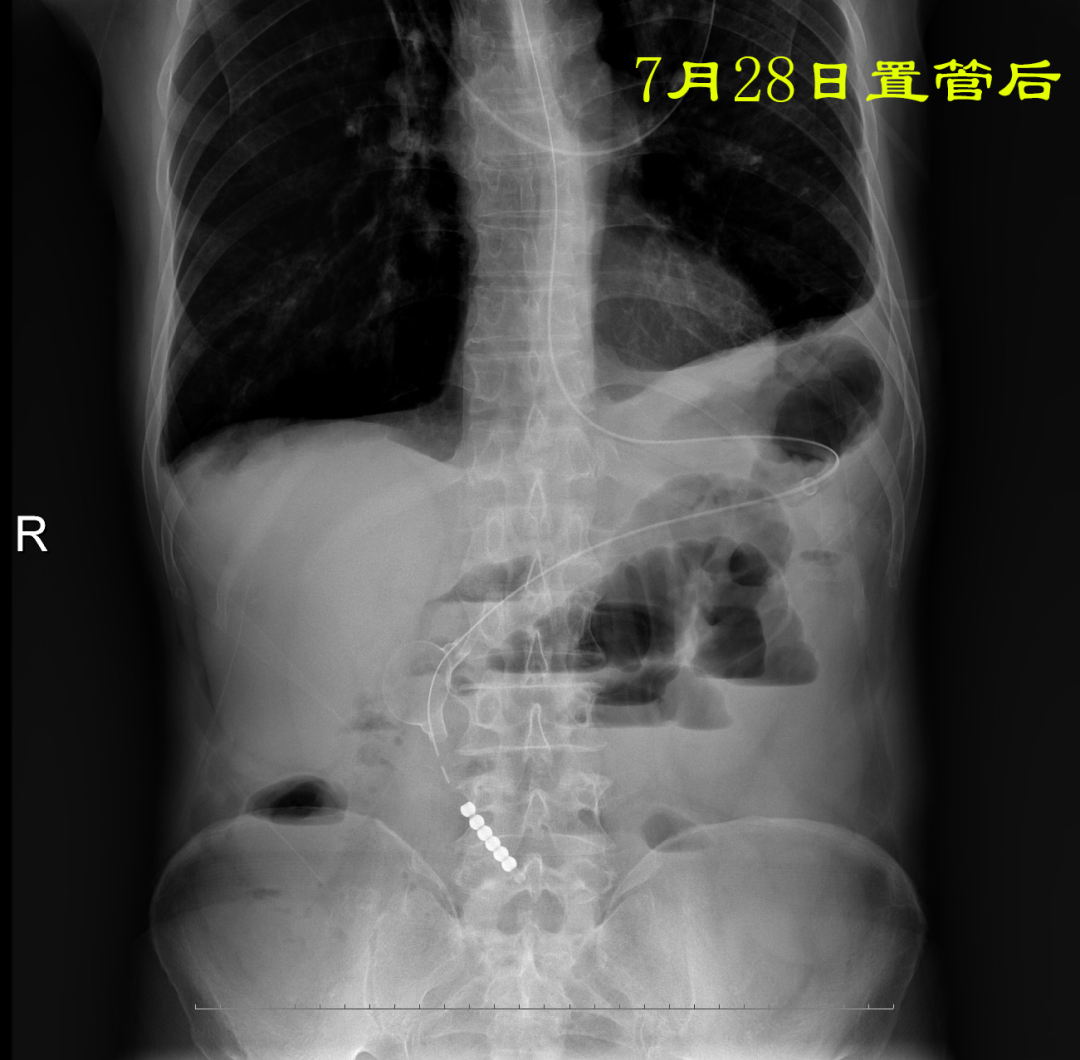

病例:患者男性,74岁,因“腹痛、腹胀伴呕吐、肛门停止排气排便20小时”于2021年7月24日入住我院普外科。患者1月前因回肠穿孔于我院普外科手术治疗,入院后明确诊断为术后粘连性小肠梗阻,经胃管引流等保守治疗无好转。因患者有严重心肺疾患,再次手术风险较大,并且术后再发粘连性肠梗阻的可能性也很大。经过与患者家属沟通后,最后决定采用胃镜引导下置入经鼻插入型肠梗阻导管技术来治疗肠梗阻。由我院消化内科副主任医师杨开余完成操作,耗时大约40分钟,患者术后第5天开始排气排便,腹痛、腹胀症状迅速消失,术后第7天拔除肠梗阻导管,恢复饮食。拔管至今已10天,患者已出院。随访患者无腹痛、腹胀,排便正常。

良好的引流是治疗肠梗阻的基本措施,低位小肠梗阻置入胃管引流常难以奏效,以往大多需要再次手术,而再次手术后粘连的几率高达70%。经鼻插入型肠梗阻导管就是将一根3米多长,内有四个腔道的管道置入十二指肠后,在重力和肠道蠕动的作用下,导管先端部将自动向前运动,直至到达梗阻部位。在导管到达梗阻部位后,可进行双对比造影检查了解狭窄病因,也可以对狭窄处进行扩张,还可以作为支架起到肠排列的治疗效果。肠梗阻导管治疗小肠梗阻属于微创型手术,具有痛苦小、疗效好、费用低、预防再次粘连等优点。

据悉,目前我省仅有为数不多的几家医院胃肠外科在开展此项技术,都是在C臂透视下经导丝置管,有X线暴露的缺点,我院现用胃镜辅助下置管可避免接触放射线。